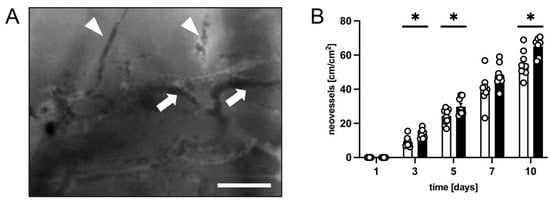

3.1. Intravital Fluorescence Microscopy